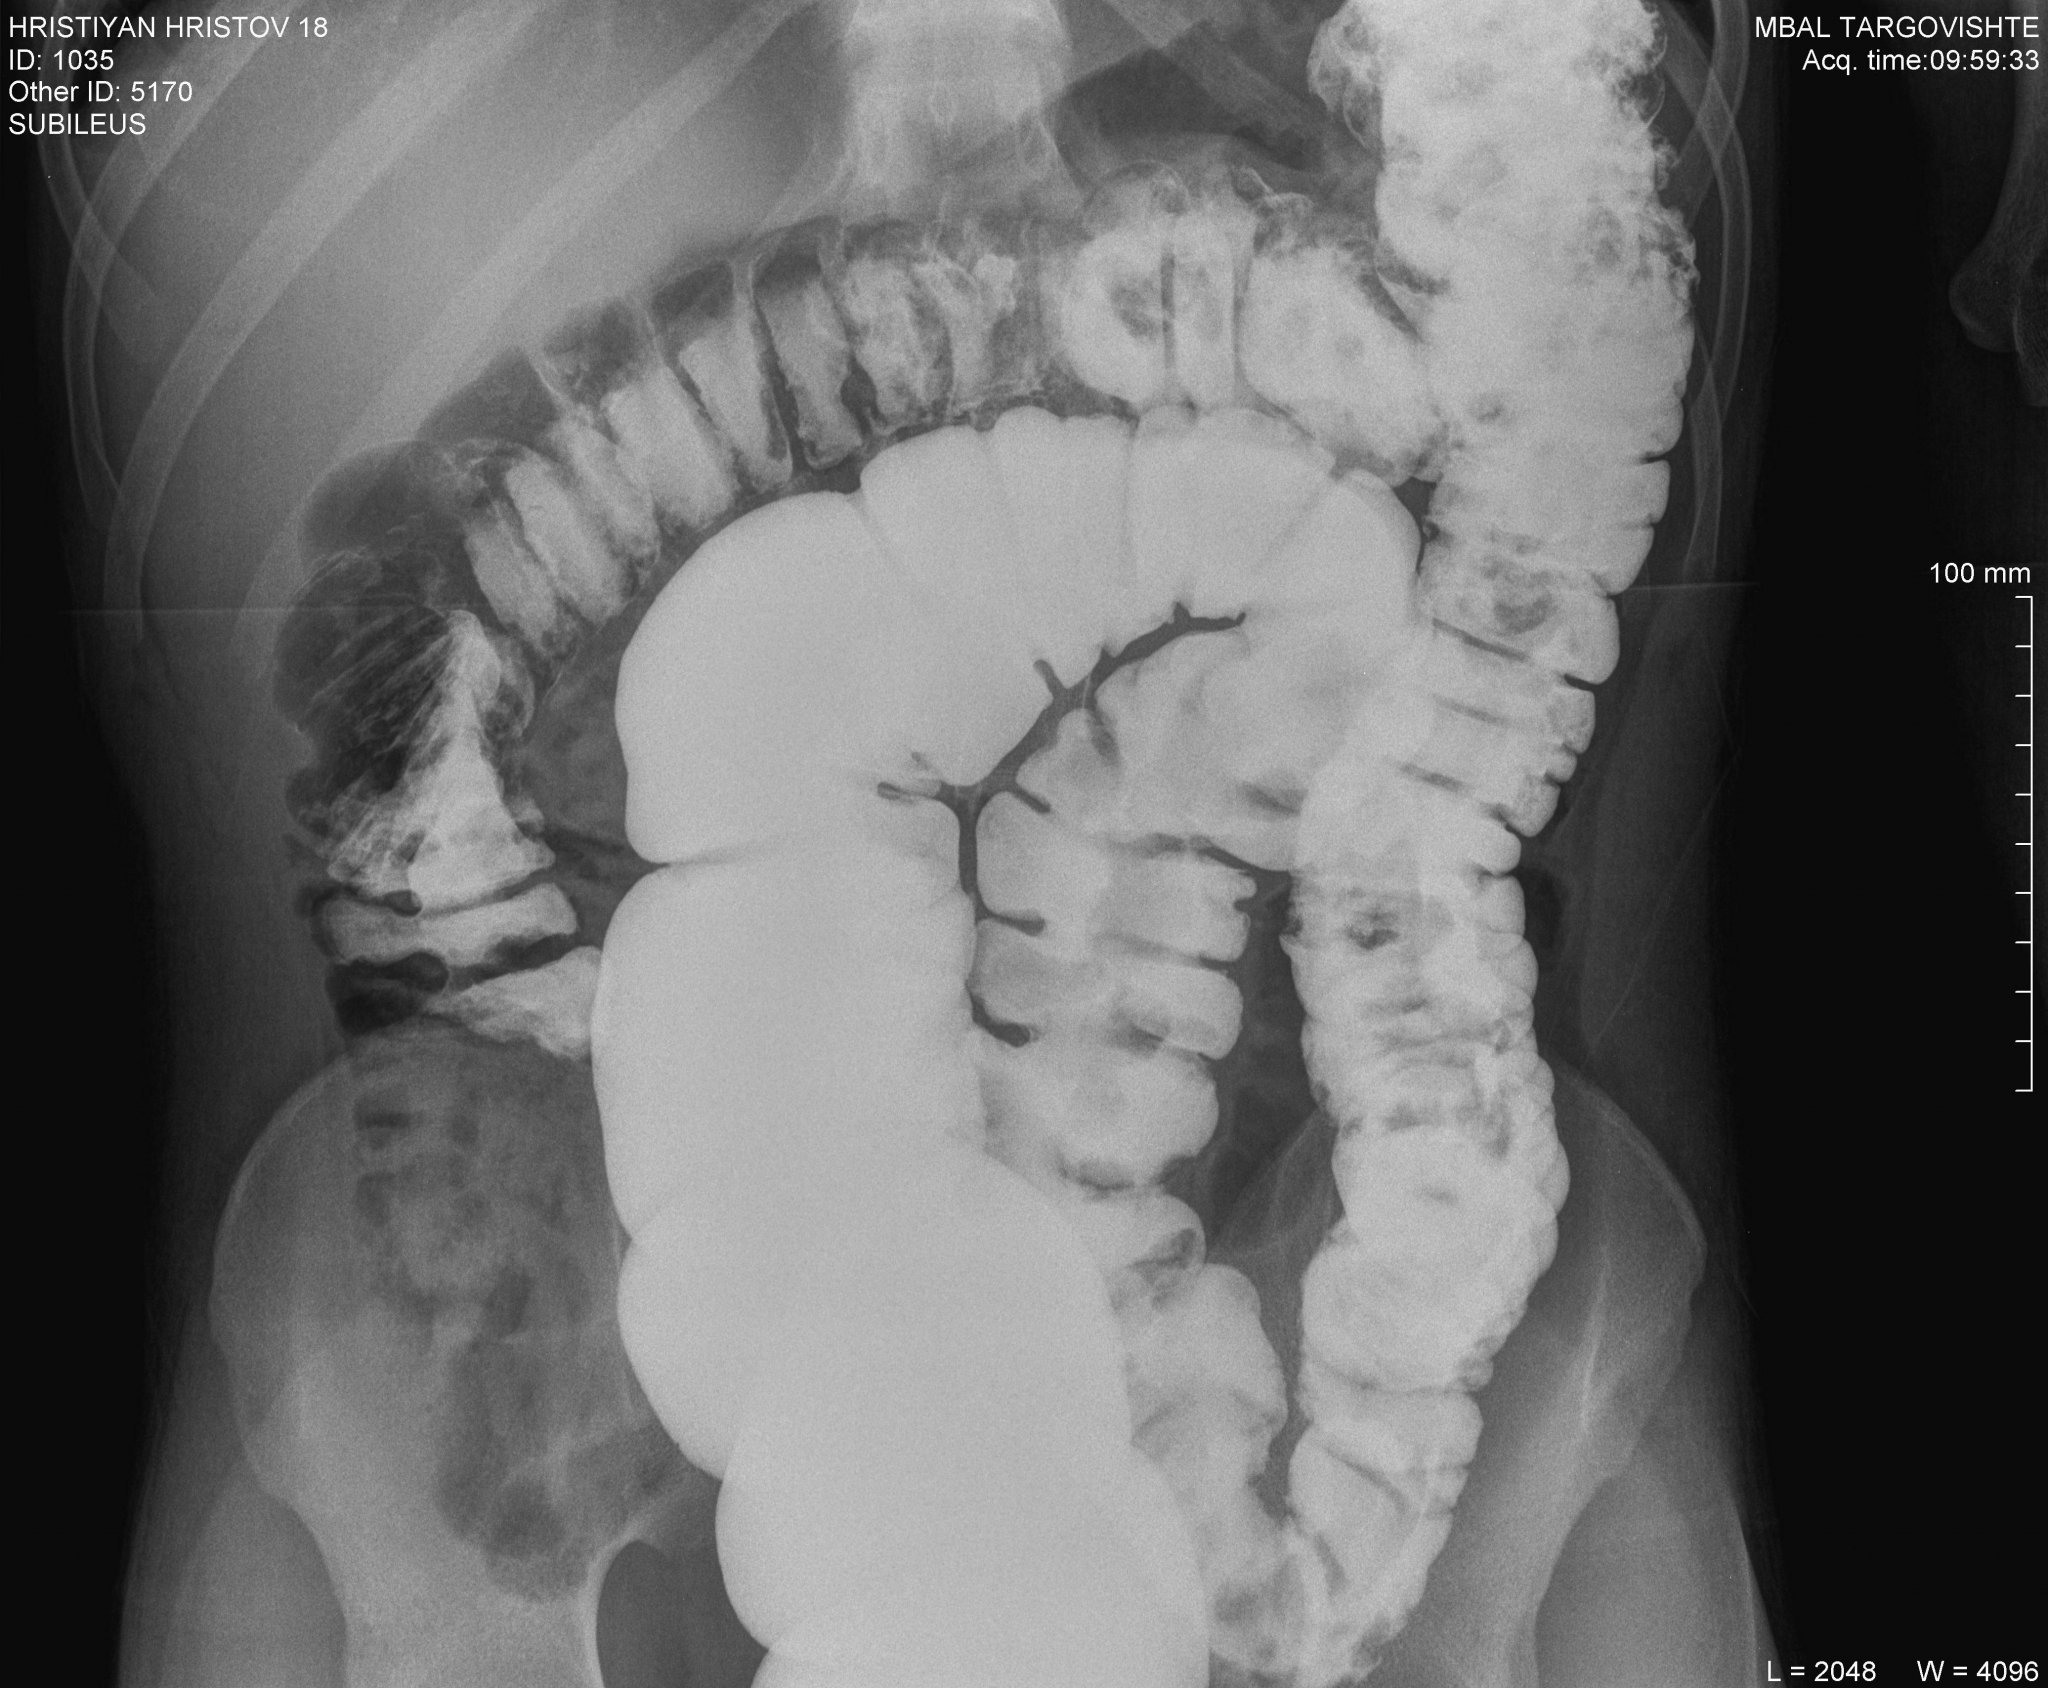

Проф.Бранков,какво можете да кажете по тази снимка?

Само по снимката мога да кажа, че има много дълго сигмоидно черво, което може да доведе до смущения в дефекацията. Но диагноза не се поставя по един рентген - трябва преглед и обстоен разпит за симптомите.